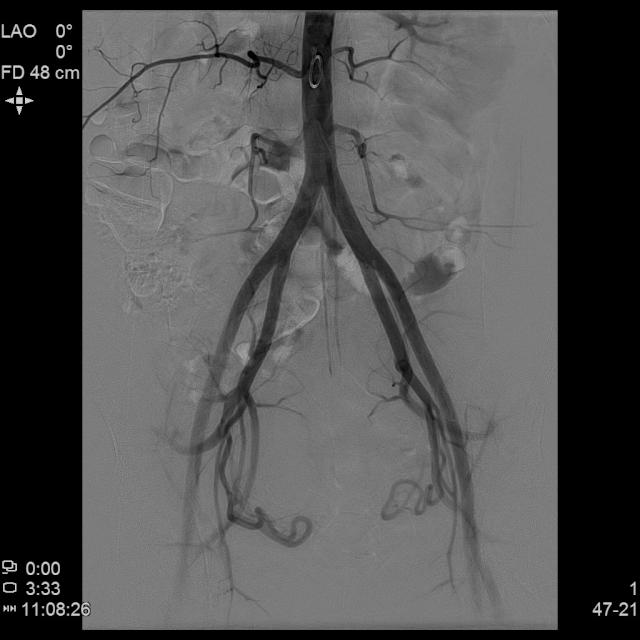

- 经桡动脉入路置入导管造影显示双侧子宫动脉明显增粗,染色丰富,子宫明显增大

- 进一步超选插管右侧子宫动脉造影确认位置

- 进一步超选插管左侧子宫动脉造影确认位置